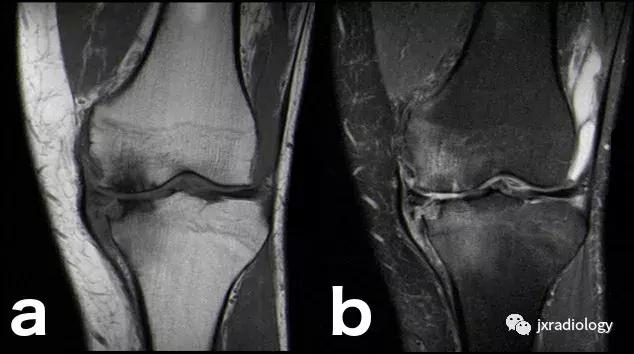

图26:局限性游走性骨质疏松症(具有位置变化的短暂性骨髓水肿综合征)(连续冠状PD-FS-WI):在一些情况下,在连续MRI上看到骨髓水肿的位置变化,这被称为局限性游走性骨质疏松症(RMO);尽管可以自愈的短暂性骨髓水肿综合征的情况更为常见,但可以在一小部分病例中转移到不同的关节,或者(甚至更罕见)转移到同一关节内的不同部位(关节内转移) ,如关于该患者所见。在这个关节内RMO病例中,没有创伤史,水肿始于股骨内侧髁,3个月后发现转移到外侧髁。